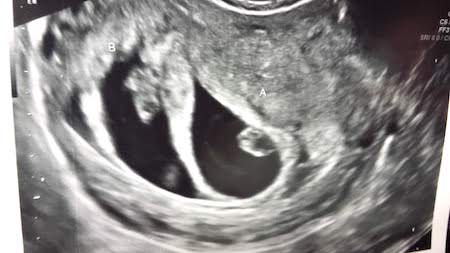

Has someone told you that you have an irritable Uterus? Are you pregnant with twins? Did you know that a twin pregnancy is an entirely different ballgame than a singleton? More tests, more monitoring, more possibility for complications. Something you might experience during a twin pregnancy is called irritable uterus, or uterine irritability, when regular contractions occur but there is no labor or cervical change.